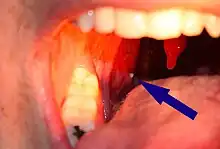

| A tonsillolith lodged in the tonsillar crypt | |

Tonsil stones, also known as tonsilloliths, are mineralization of debris within the crevices of the tonsils.[1][3] When not mineralized, the presence of debris is known as chronic caseous tonsillitis (CCT).[1] Symptoms may include bad breath.[1] Generally there is no pain, though there may be the feeling of something present.[1]

Larger tonsil stones may cause recurrent bad breath, which frequently accompanies a tonsil infection, sore throat, white debris, a bad taste in the back of the throat, difficulty swallowing, ear ache, and tonsil swelling.[8] A medical study conducted in 2007 found an association between tonsilloliths and bad breath in patients with a certain type of recurrent tonsillitis. Among those with bad breath, 75% of the subjects had tonsilloliths, while only 6% of subjects with normal halitometry values (normal breath) had tonsilloliths. A foreign body sensation may also exist in the back of the throat. The condition may also be an asymptomatic condition, with detection upon palpating a hard intratonsillar or submucosal mass.

A tonsillolith protrudes from the tonsil